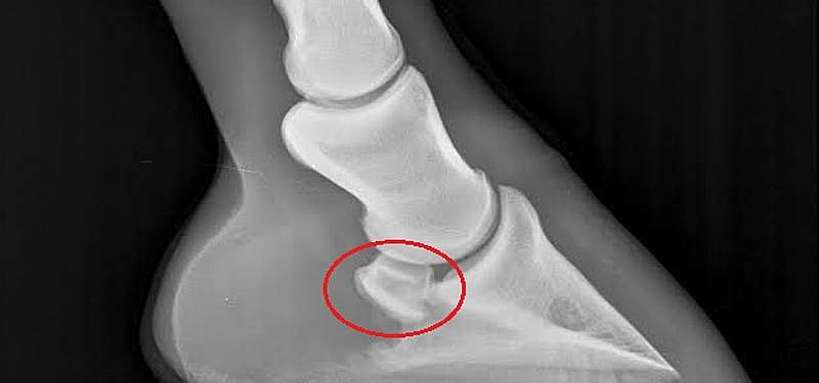

Elle se caractérise par une atteinte de l'os naviculaire et / ou des formations anatomiques environnantes ( tendon perforant, ligaments sésamoïdiens ou membranes synoviales)

C’est une dégénérescence progressive qui touche principalement l’os naviculaire (un petit os situé à l’arrière du pied), mais aussi les structures environnantes : ligament suspenseur du naviculaire, bourse podotrochléaire, tendon fléchisseur profond…

Le diagnostic se fait par examen locomoteur, test à la pince, bloc anesthésique, et surtout radiographies. Dans certains cas, une IRM est nécessaire pour visualiser les tissus mous.